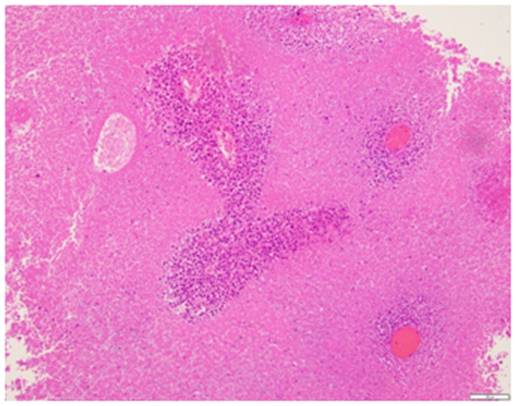

A 52 year old G1P1001 female with a history of hypertension, hyperlipidema, depression, and schizoaffective disorder presented with the primary complaint of a painful left sided vaginal mass. She also complained of irregular heavy menses for the past three months. On pelvic exam, the vaginal mass was diagnosed as a left Bartholin gland abscess that measured 2x3cm and was noted to be indurated. The remainder of the pelvic exam was unremarkable. The patient was offered incision and drainage for which she declined. She was started on Augmentin. Perimenopause was thought to be a contributing factor of the patient’s irregular menstrual pattern. As part of screening guidelines, Papanicolaou smear was performed and was found to be remarkable for atypical glandular cells of undetermined significance. Endometrial biopsy (EMB) was recommended. The patient was lost to follow up for two months. She eventually returned to clinic and reported improvement in the abscess after antibiotics, but recurrence after discontinuation. During her follow up visit, EMB and incision & drainage of the Bartholin abscess with placement of Word catheter was performed. However, due to the exuberant amount of indurated tissue expressed from the Bartholin abscess, a tissue specimen of the Bartholin abscess were sent to pathology for evaluation. The pathology report returned a poorly differentiated malignant neoplasm favoring carcinoma for the Bartholin gland sample as well as the endometrial biopsy sample. The tumor was described as poorly differentiated and consisting of enlarged nuclei with vesicular chromatin, perinuclear clearing, occasional prominent nucleoli, moderate amounts of amphophilic delicate cytoplasm, and increased mitoses (Figures 1 & 2). There was also extensive tumor necrosis seen in the specimens (Figure 3). The patient underwent CT of her chest, abdomen, and pelvis, as well as a PET CT of the skull to thigh. Her CT revealed a 10.8 cm poorly defined endometrial and myometrial neoplasm, with metastatic disease to the right iliac node, right parametrial nodes, periaortic lymph nodes, and bilateral adrenal glands. There were no other significant findings on CT. Her PET scan showed prominent Fluorodeoxyglucose (FDG) activity in the uterine mass and left adrenal mass, with a smaller amount of FDG activity in a large right pelvic lymph node adjacent to the uterine mass, with no other contributory findings (Figure 4). She was referred to the care of medical oncology, and during the patient’s Gynecology Tumor Board case presentation the pathologists concluded that her poorly differentiated cancer was uterine in origin. Due to the extent of metastatic disease she was recommended medical management. She was started on a Paclitaxel and Carboplatin chemotherapy therapy.

Figure 3 Medium power view showing extensive tumor necrosis. The viable tumor is surrounding blood vessels and the adjacent necrotic tissue shows outlines of the necrotic atypical tumor cells (H&E, 10x).